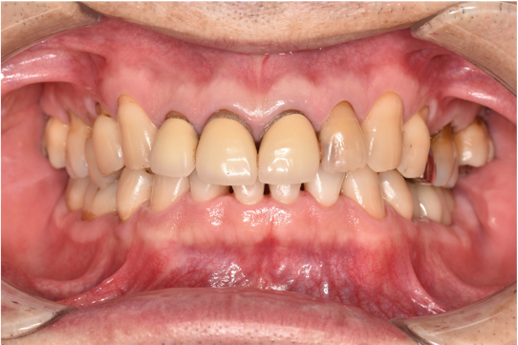

治療後

| 行ったご提案・治療内容 | 初診時に撮影したレントゲン、口腔内写真、歯周検査の結果を用いて、着色除去、歯周病治療の必要性をお伝えしました。 初診時は歯ブラシのお話しをさせていただき、セルフケアの方法について説明を行い、その後気にされてみえた着色除去、歯肉縁上歯石除去を行いましました。 歯肉の炎症がある程度落ち着いたところで、後日、再評価を行い歯周治療へ移行しました。 |

| 術後の経過・現在の様子 | 術後の経過は順調で、着色除去後、鏡でお口の中を確認をしていただいたところ、「とても綺麗になった!ご丁寧にありがとうございます」と仰っていただけました。 |